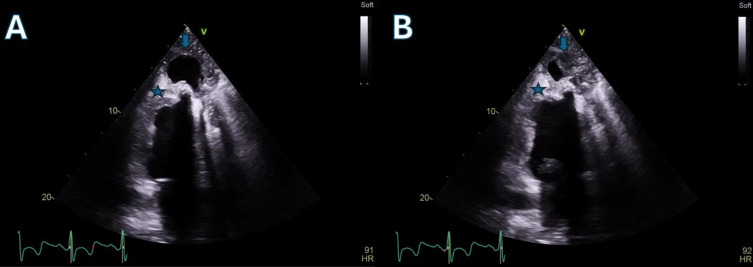

左心室辅助装置(lvad)已成为晚期心力衰竭治疗的重要方式,有时可作为恢复的桥梁。一例30多岁酒精性扩张型心肌病患者在严重心功能不全后行左心室辅助装置植入。6年后,心肌恢复良好,LVAD移植成功。植体术后2年,患者继续存在高危生活方式(如吸烟、饮酒),最终因跌倒并左胸外伤发展为左胸假性动脉瘤。手术修复发现感染,用靶向抗生素治疗。本病例表现出罕见的超声心动图表现,并强调了左心室辅助器移植的复杂性,特别是在患者持续高风险生活方式的情况下。据我们所知,感染的左心室假性动脉瘤并发左心室辅助器移植以前没有报道过。因此,其管理和长期结果无法使用循证指南进行评估。

Left ventricular assist devices (LVADs) have become an important modality of treatment in advanced heart failure, serving sometimes as a bridge to recovery. A subject in his 30s with alcohol-induced dilated cardiomyopathy underwent LVAD implantation following severe cardiac dysfunction. After six years, a sufficient myocardial recovery led to successful LVAD explantation. 2 years post-explant, the patient continued high-risk lifestyle behaviors (like smoking and drinking alcohol) and eventually developed a left thoracic pseudoaneurysm due to a fall with left chest trauma. Surgical repair revealed infection, treated with targeted antibiotics. This case shows a rare echocardiographic presentation and underscores the complexities of LVAD explantation, particularly in patients continuing high-risk lifestyle behaviors. To our knowledge, an infected left ventricular pseudoaneurysm complicating LVAD explantation has not previously been reported. Thus, its management and long-term outcomes could not be assessed using evidence-based guidelines.